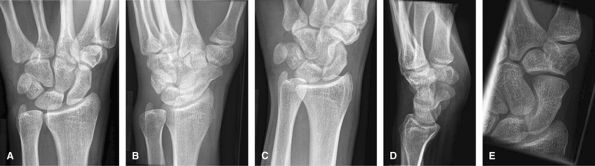

Trauma

Additional scaphoid views include oblique and ulnar

deviation with cranial angulation. These are good to assess for most

aspects of trauma including fracture, subluxation, or dislocation. Of

note, the lateral view can only be used to assess alignment when the

volar aspect of the pisiform projects between the scaphoid and capitate.

MRI is a useful adjunct to assess for occult injury, intercarpal

ligament injury, triangular fibrocartilage complex injury, mass, or

synovitis.

![]() |

Figure 6 (A) PA wrist. (B) Ulnar oblique wrist. (C) Radial oblique wrist. (D) Lateral wrist. (E) Navicular view.